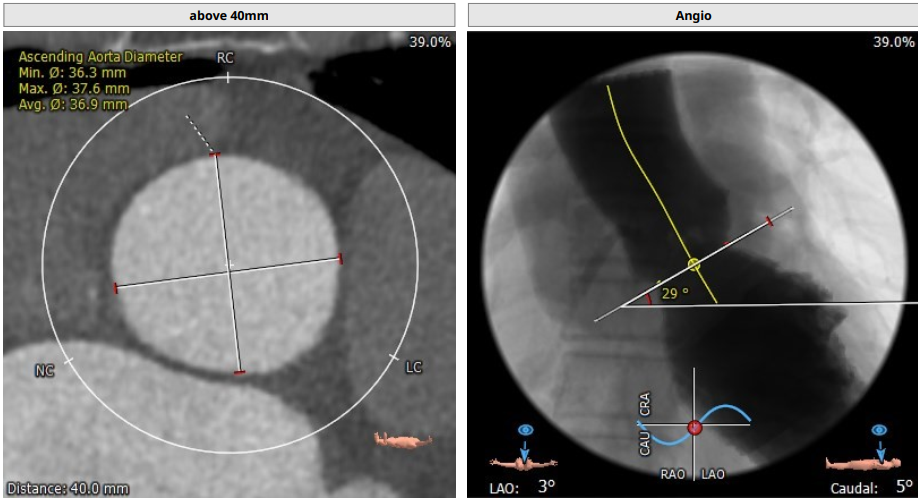

Tepy1型二叶瓣,中度钙化,瓣环直径25.6mm,LVOT32.5mm,窦部短轴最窄处22.8mm,综合考虑DOWNSIZE选择L26或者L29瓣膜。冠脉高度尚可,STJ较高,以及二叶瓣均可降低冠脉风险,整体评估冠脉风险较小,决定术中使用22mm球囊预扩确认冠脉风险及瓣膜选择。

入路情况较为特殊,右股入路扭曲,左股尚可,腹主迂曲,上大鞘和过输送器时应轻柔,以防止血管并发症。决定左股作为主入路,左桡作为辅路。弓部呈锐角,过弓时应注意血管损伤,必要时借助抓捕器。